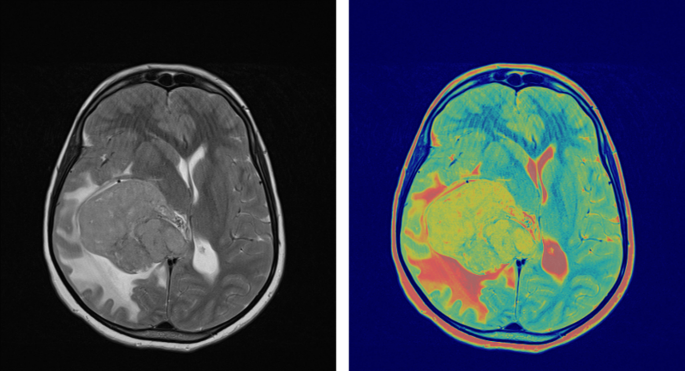

To evaluate surgical efficacy and determine the presence of any residual tumor tissue, the integration of follow-up MRI with contrast enhancement within a 48-hour timeframe following surgery assumes paramount importance. Such subsequent examinations often reveal contrast enhancement attributed to surgical intervention and the effects of radiotherapy. As shown in Fig. 1, pre-surgical FLT-PET/MRI brain imaging highlights glioblastoma contrast enhancement on Gd-enhanced MRI and FLT-PET activity concentration. The PET image was normalized to create a Gd-enhanced T1-weighted MRI matrix. While FLT PET and contrast-enhanced MRI images of GBM offer invaluable insights and information, it is crucial to consider and account for the aforementioned limitations. Therefore, exploring alternative imaging methodologies and approaches is imperative to enhance the accuracy of diagnosis and improve the efficacy of treatment monitoring, ultimately augmenting patient outcomes and prognoses.

To enhance the precision of tumor delineation in PET/MRI imaging, it is essential to refine the imaging process by excluding structures such as the skull bone and meninges. As shown in Fig. 2, this refinement involves copying the PET delineation onto the MRI image to define initial boundaries (Fig. 2a and b). Subsequently, the MRI is employed to exclude the skull bone and meninges from the region of interest (ROI) (Fig. 2c). The delineation is further enhanced using adaptive thresholding techniques (Fig. 2d). These refinements are critical for achieving accurate boundary definitions and improving diagnostic precision.

Contrast-enhanced MRI and FLT-PET imaging provide complementary insights into tumor characterization. As illustrated in Fig. 3, the blue areas in the contrast-enhanced MRI image (Fig. 3a) represent active tumor regions identified through increased uptake of the contrast agent. Meanwhile, the red delineated regions in the FLT-PET image (Fig. 3b) highlight tumors with high proliferative activity, offering a distinction from the surrounding tissues. This combined imaging approach enhances the accuracy of tumor detection and characterization, aiding in treatment planning and monitoring.